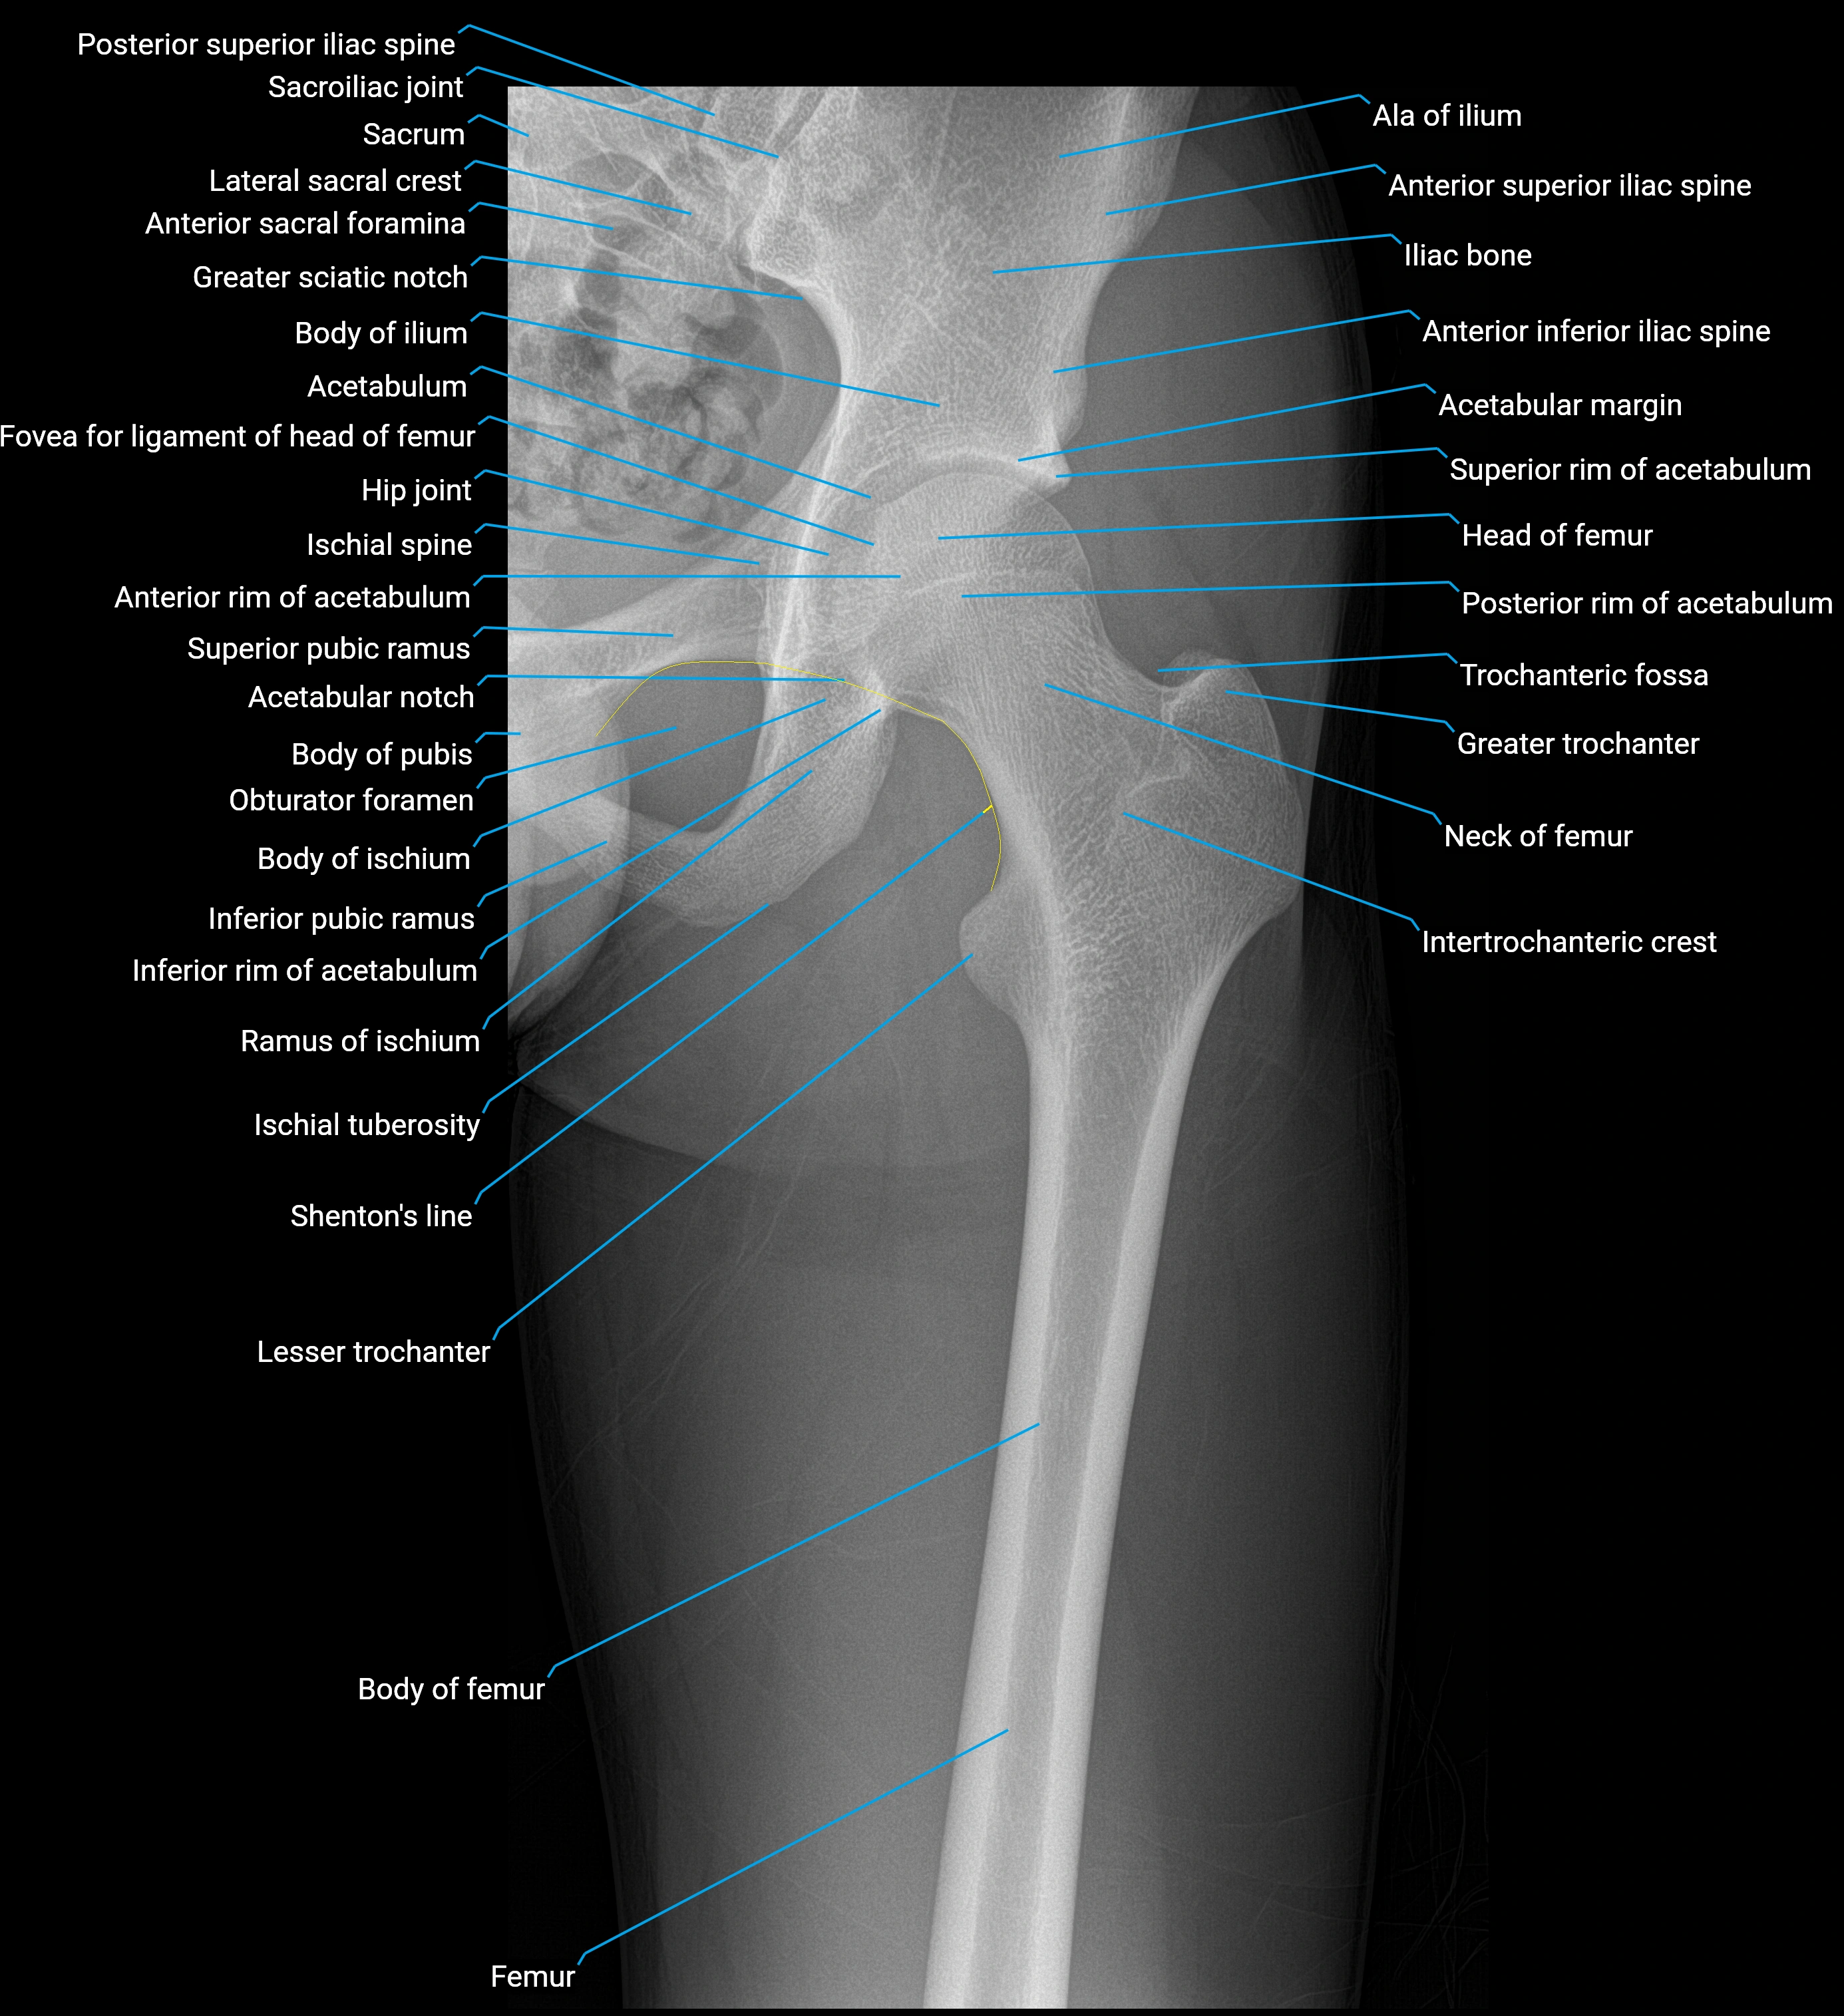

The acetabular labrum is a fibrocartilaginous ring that surrounds the rim of the acetabulum in the hip joint. It deepens the hip socket, increases joint stability, and maintains a suction seal that preserves negative intra-articular pressure. Structurally, the labrum transitions from hyaline cartilage of the acetabulum to dense fibrocartilage at its free edge.

It is triangular in cross-section, with its base attached to the acetabular rim and its apex projecting toward the femoral head. The labrum is most robust superiorly and anteriorly, where load bearing is greatest, and relatively thinner inferiorly.

Structure and Relations

• Superior and anterior labrum: thickest portions, stabilizing against anterior dislocation

• Inferior labrum: blends with the transverse acetabular ligament bridging the acetabular notch